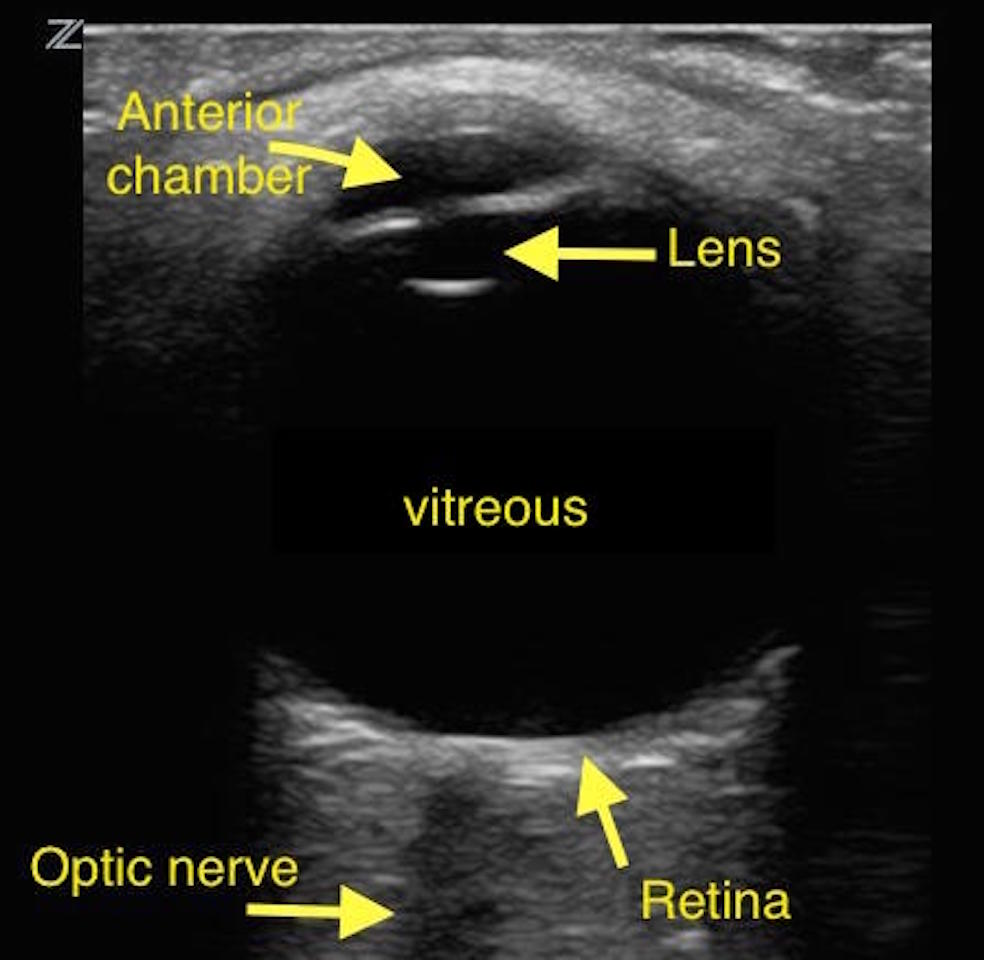

An anatomy ultrasound is often carried out between the 18th and 22nd week of gestation. Ultrasound waves are produced by a transducer, which can both emit ultrasound waves, as well as detect the ultrasound echoes reflected back. Throughout this course the fundamental use and clinical application of ultrasound as a diagnostic tool will be explored through seven key examinations.